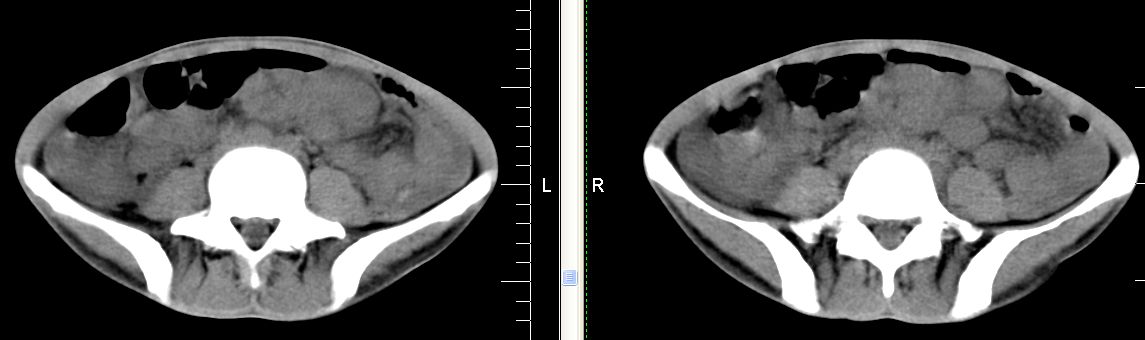

m 29 肺tb患者,目前诉下腹疼痛 t39度 腹韧,有压痛,可触及3x4cm包块

脾脏多发低密度灶,肠系膜及腹膜后见多发大小不等结节状影,右结肠旁沟见低密度影,结合病史考虑:脾结核,肠系膜及腹膜后淋巴结结核,少量腹水。

脾脏多发低密度灶,左侧肾上腺见块状病灶,密度不均,盲肠升结肠肠壁明显增厚,左下腹似可见肠壁增厚,肠系膜及腹膜后见多发大小不等结节状影,右结肠旁沟见低密度影,1淋巴瘤可能大,2结合病史考虑:脾结核,左侧肾上腺结核,肠系膜及腹膜后淋巴结结核,少量腹水待除外,

考虑脾结核及腹腔结核感染,阑尾区结核脓肿不排除